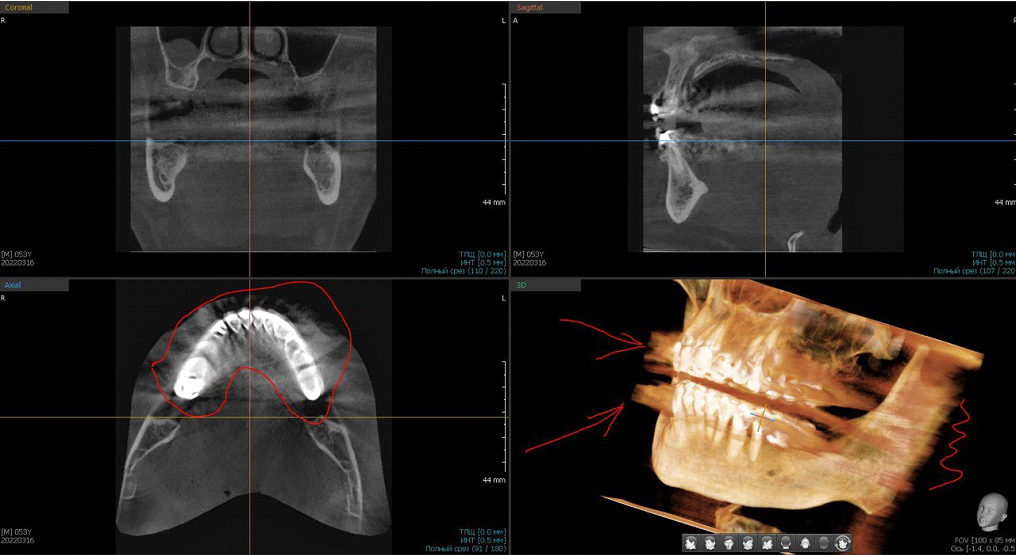

Видно отражение от металла, его дают множественные снимки

Фронтальная панорама (совмещение нескольких снимков). Прямоугольник — имплантат, его металл отражает излучение, но здесь включён постобработчик, который компенсирует гало-эффект. В овале зуб с пролеченными каналами, в каналах контрастный материал. Стрелка — зуб с живым нервом и пульпой.

Металлы, соответственно, дают очаги затемнения, как видите.